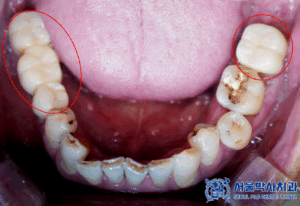

확인해보니,

치아가 상실된 부위도 많고

남아있는 치아들이

흔들리는 상황이였는데요.

왼쪽 아래 사랑니를 포함한 큰어금니는

맞닿는 위 치아가 없어

정출되어 있는 상황이였고

또한, 왼쪽 아래 치아는

맞닿는 위 치아의 상실로 인해

정출되어 교합을 방해할 수 있어,

신경치료 후 크라운 치료를 진행하였습니다.